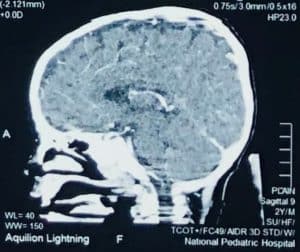

Cerebral CT scan with contrast shown as axial, coronal, and sagittal thickness of 5 mm, consistent with CVST, and maxillary sinusitis (Figure 1).

Figure 1: Image CT scan at first diagnosis

Neuroimaging showed thrombosis in more than 1 sinus, and overall thrombosis was located mainly in deep compared to superficial sinuses, 70% vs. 30%, respectively [10]. As in our reported case, cerebral TDM with contrast showed axial, coronal, and sagittal thickness of 5 mm, consistent with CVST. Sinusitis of the bilateral ethmoid and inferior sagittal sinus thrombosis was suggested.